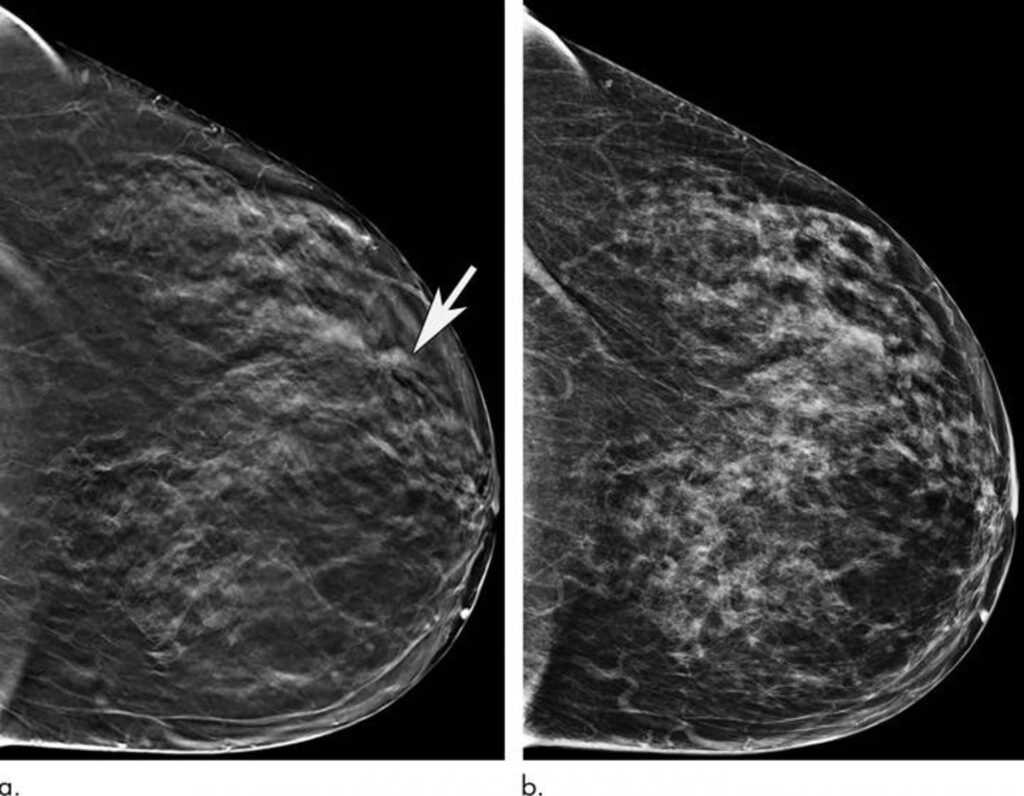

Almudena Quintana Morgado, directora general Asistencial del Servicio Madrileño de Salud (Sermas), ha asegurado la eficiencia del Programa de Detección Precoz del Cáncer de Mama (DEPRECAM) en Madrid, destacando que no hay listas de espera estructurales y que el tiempo medio de espera es de 34 días para realizar una mamografía, garantizando además que todas las pacientes son informadas sobre los resultados de sus pruebas.

Durante 2023, el programa ha detectado 2.576 casos sospechosos de cáncer, requiriendo pruebas adicionales para confirmar el diagnóstico. Además, la tasa de detección de cáncer está en 5,4 casos por cada mil mujeres examinadas, con un alto porcentaje de detección en estadios iniciales, lo que facilita tratamientos menos invasivos y mejora las tasas de curación.